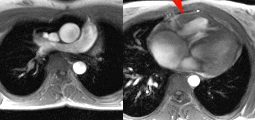

Envahissement tumoral de la paroi latérale du VG avec hypersignal T2 (séquence STIR) et hypersignal post-gadolinium (PSIR) chez un patient de 49 ans aux antécédents de séminome une quinzaine d’année auparavant avec récidive l’année précédente, traitée par chimiothérapie et extension sous forme de nodules pulmonaires et de métastase cérébrale traitée par radiothérapie. La paroi latérale infiltrée est hypokinétique avec FEVG abaissée à 54%.